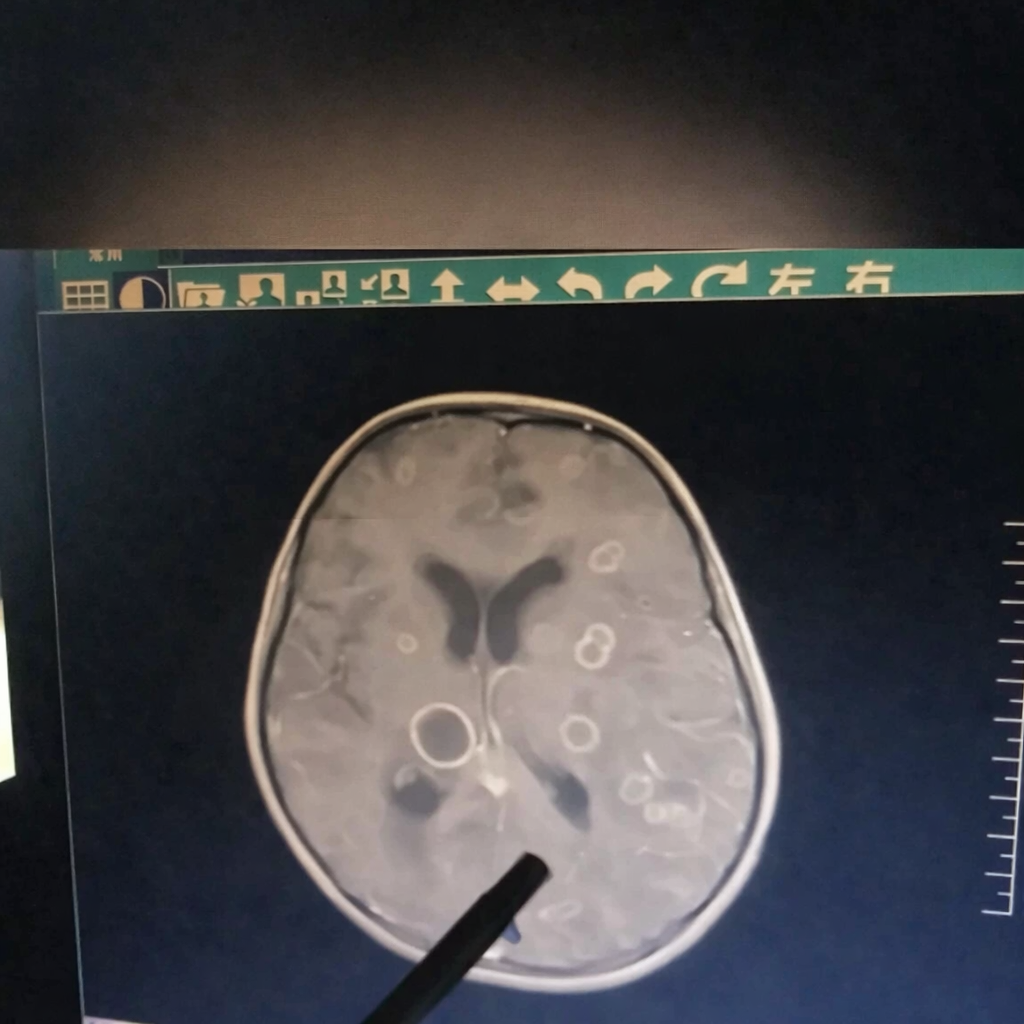

Mới đây, một bé gái 6 tuổi ở Trung Quốc bị sốt liên tục suốt 17 ngày, dần rơi vào tình trạng lơ mơ, rối loạn ý thức và được chuyển gấp tới Bệnh viện trực thuộc Đại học Trịnh Châu (Trung Quốc). Kết quả kiểm tra khiến các bác sĩ không khỏi bàng hoàng: trong não của đứa trẻ xuất hiện hơn chục ổ tổn thương lớn nhỏ, giống như bị “gặm nhấm” từng mảng.

Bác sĩ cho biết, nếu đến muộn thêm vài ngày, tổn thương có thể lan rộng đến mức đe dọa trực tiếp tính mạng.

Sau khi chọc hút dịch trong các ổ tổn thương để xét nghiệm, “hung thủ” cuối cùng cũng lộ diện: nấm Aspergillus fumigatus, hay còn gọi là nấm khói.